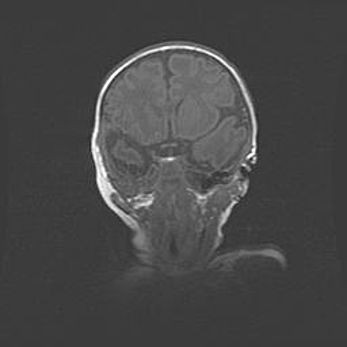

Церебральная ишемия II.

Возраст: 5 дней

Вес: 3400 г

Пол: женский

Окружность головы: 35 см

Срок гестации: 39 недель

Церебральная ишемия – это заболевание, характеризующееся недостаточностью (гипоксией) либо полным прекращением (аноксией) снабжения мозга кислородом по причине закупорки одного или нескольких сосудов. Это приводит к  что метаболическим расстройствам различной степени тяжести в тканях головного мозга, развитию коагуляционных некрозов и гибели нейронов.